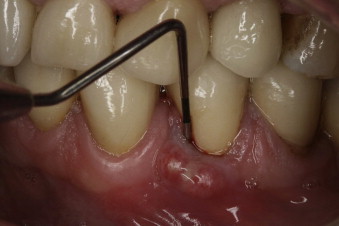

A pocket between the gum and the tooth, near the fracture, where the gum essentially detaches from the tooth

The typical indication of a dental fistula or sinus tract is a bump that develops on the gum tissue or gingiva, where it’s called a gum boil, or in proximity to an abscessed tooth. The bump might alternatively appear and disappear, and is a sign that infection exists and your body is using the fistula to drain it. Since draining releases the pressure of the abscess, the fistula itself is often not painful, although many patients report an unpleasant taste.